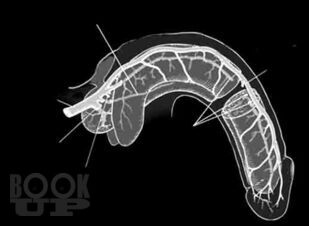

В руководстве представлены общепринятые и новейшие технологии диагностики и лечения актуальной проблемы уроандрологии – веногенной эректильной дисфункции. Подробно описаны методики традиционных общеклинических, ультразвуковых и рентгеновских методов обследования, а также дополнительных методов диагностики – компьютерной и магнитно-резонансной томографии, лазерной флоуметрии. Обоснована эффективность консервативного медикаментозного лечения и возможность использования экстракорпоральной ударно-волновой терапии. Описаны традиционные хирургические операции, а также альтернативные микрохирургические и рентгенэндоваскулярные вмешательства. Представлена патоморфологическая характеристика структурно-функциональных изменений полового члена у больных с веногенной эректильной дисфункцией. Доказано наличие варикозной болезни органов малого таза и ее влияния на мужское здоровье. В приложении собраны все необходимые диагностические тесты – опросники для пациентов.